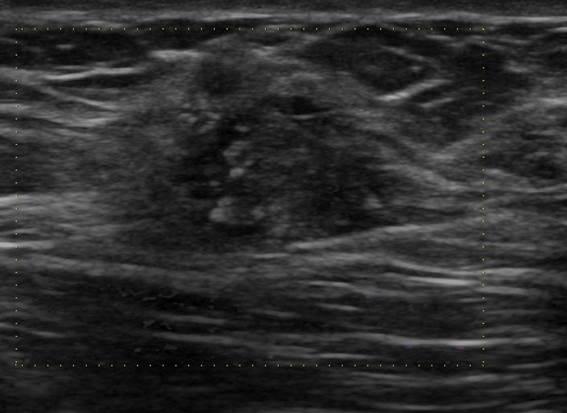

Ung thư vú

Ung thư vú - Ảnh 4

» Thông tin: Nữ giới – 41 tuổi.

» Lâm sàng: Khối tuyến vú.